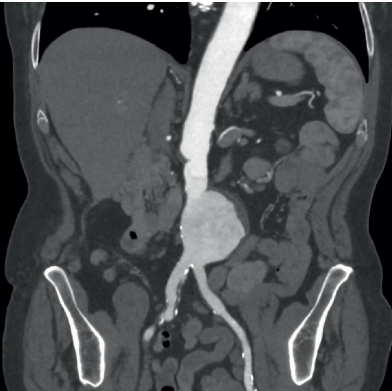

What is shown in the image below?

A

Fusiform AAA